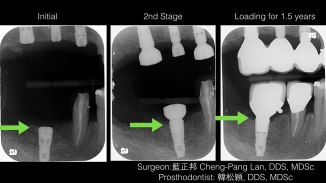

Horizontal Ridge Augmentation – Block Graft + Guided Bone Regeneration – Case C

Horizontal ridge augmentation-Block Graft.001 Horizontal ridge augmentation-Block Graft.002 Horizontal ridge augmentation-Block Graft.003